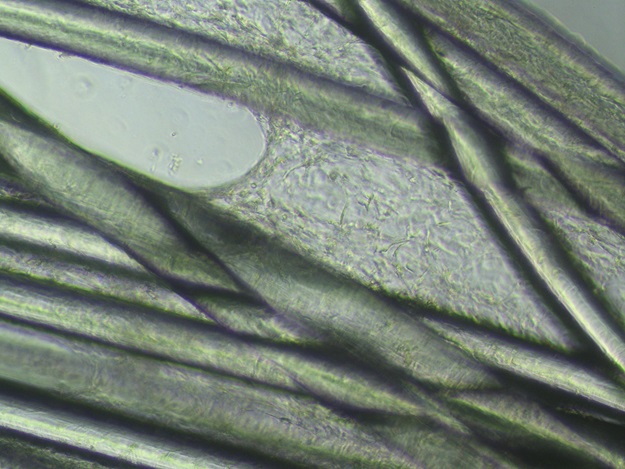

Bó sợi polymer sinh học của dây chằng nhân tạo được thử nghiệm hoạt tính sinh học trên tế bào mô sợi trong ống nghiệm sau 10 ngày, cho thấy có sự bám dính và phát triển của cụm tế bào rõ rệt. Ảnh: Nhóm nghiên cứu